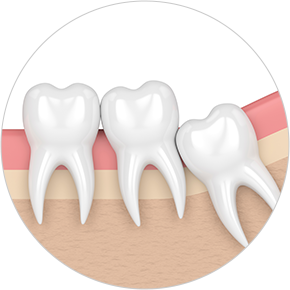

Some wisdom teeth erupt normally, but others may erupt at an angle, horizontally, or remain fully impacted. Wisdom teeth that do not erupt properly can disturb the dental arch and are difficult to clean, which may lead to decay of adjacent molars. In such cases, extraction is recommended.

• Horizontally

impacted wisdom tooth

• Angulated

• Vertically